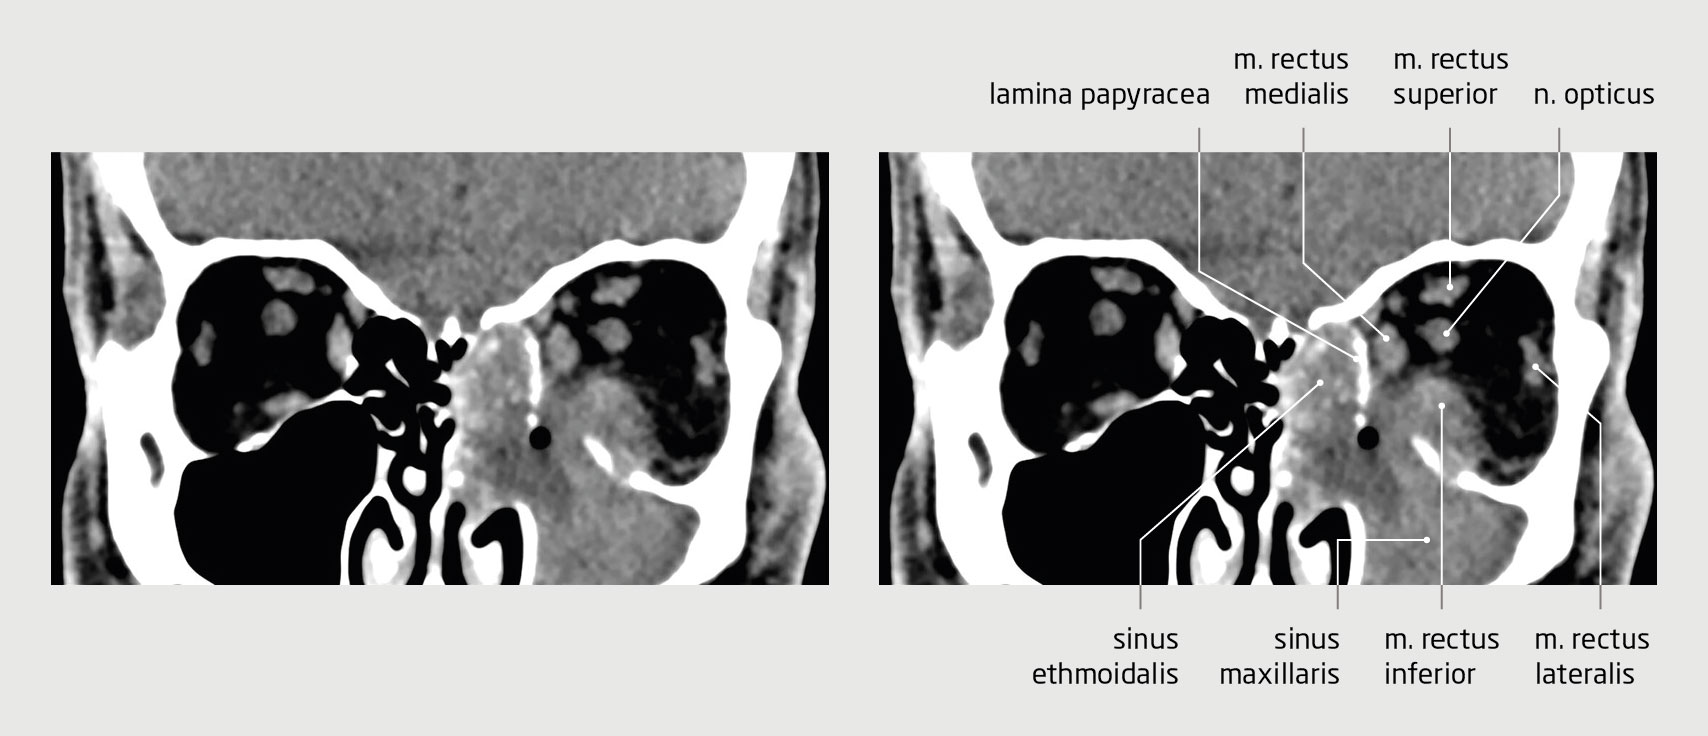

Figuur 2 | CT-scan van de orbita

Coronale CT-scan van de orbita van de 53-jarige patiënt. De sinus maxillaris en de etmoïdcellen aan linkerzijde zijn volledig gesluierd. Ook is zichtbaar dat de sinusitis is doorgebroken naar de orbita. Daarbij is de m. rectus inferior verdikt. Er was sprake van proptosis van de linker oogbol (niet zichtbaar op deze coupe).